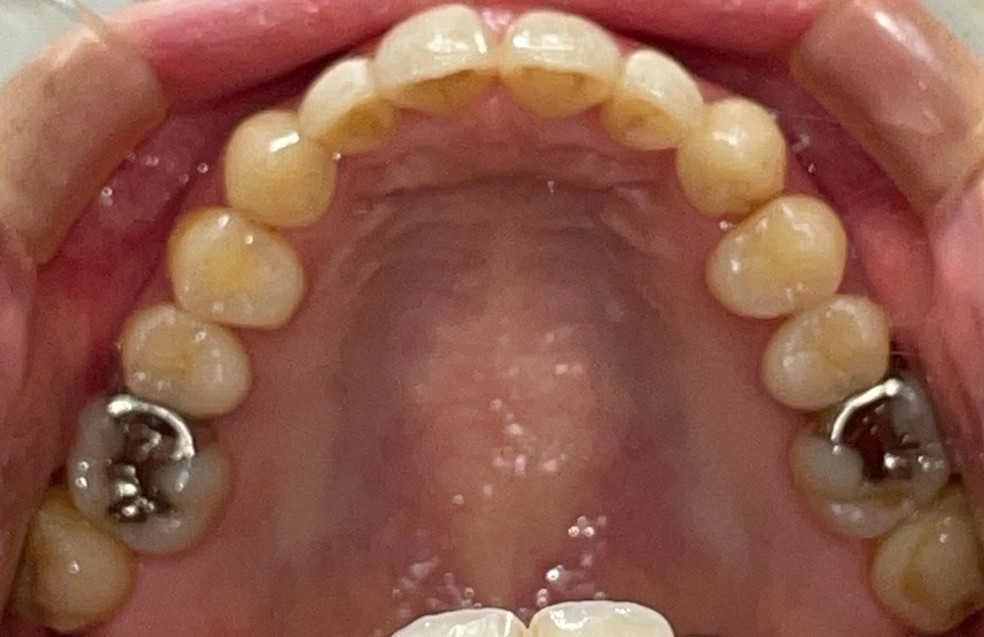

Before

After

矯正の種類 / invisalign GO

年齢・性別 / 40代女性

主訴  /  叢生

治療期間 / 12ヶ月

費用 / 簡易検査 5,000円(税別) 精密検査 30,000円(税別)

両額マウスピース 450,000円(税別)  両額リテイナー料 60,000円(税別)

※マウスピース交換時別途調節料3,000円(税別)

副作用 / 口内炎・歯の移動に伴う痛み・知覚過敏 ※数日で収まる場合が多いです

リスク / 後戻り防止の為、夜のみマウスピースで保定を指示